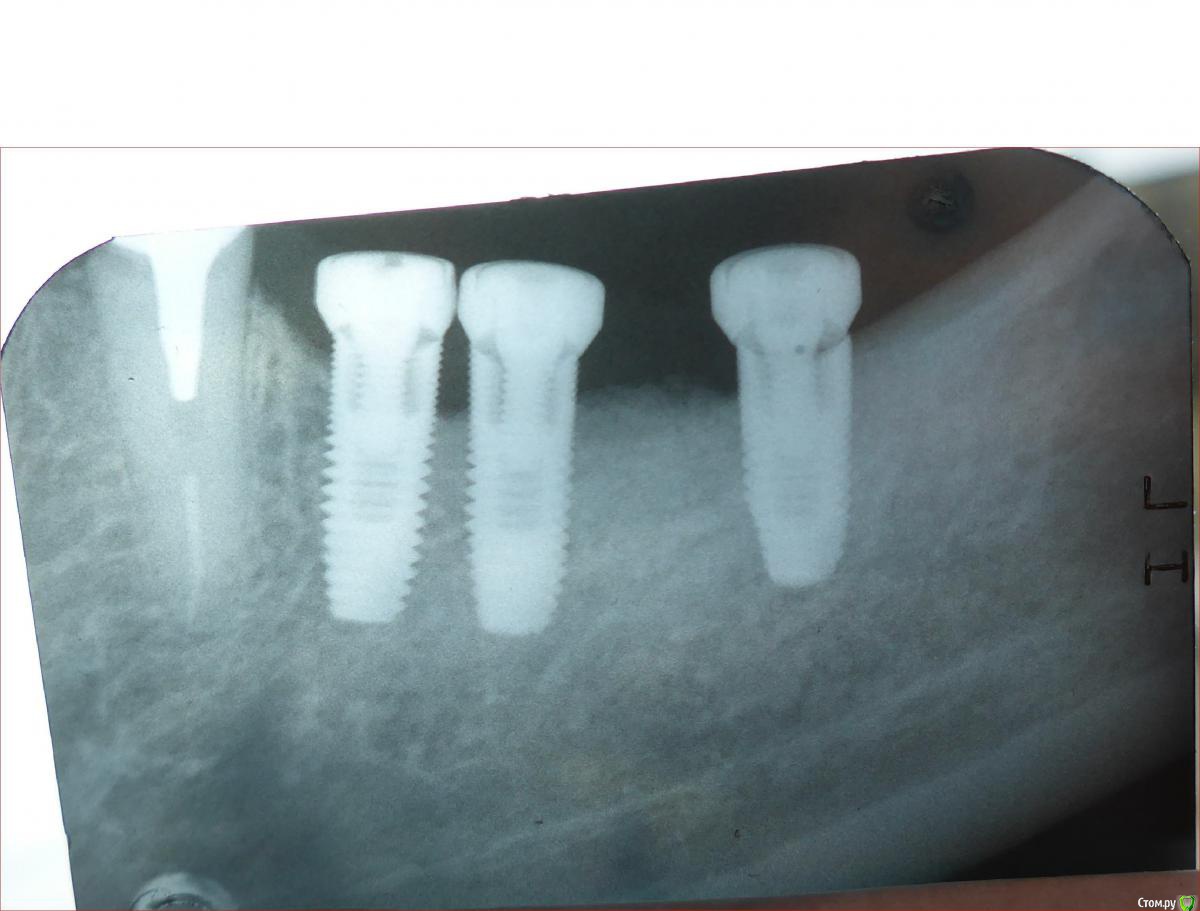

Коша Опубликовано 17 сентября, 2016 Поделиться Опубликовано 17 сентября, 2016 Здравствуйте Уважаемые доктора!Такая ситуация: Я хотел восстановить 2 отсутствующих зуба 6и7 снизу справа.Решил поставить импланты.Хирург установил их, но ортопед сказал, что на так тесно установленные импланты он два зуба не перекроет, надо еще один ставить.Хирург установил.Ортопед решил установит 2а зуба на три импланта. Говорит так надежнее.Установленные импланты U-impl Inter- первые два 3.5х10, третий 3.5х8.5.Но я прочитал, что при близко установленных имплантах, между ними может произойти рассасывание кости. Вот я теперь и волнуюсь.Абатменты еще не заказывали. Стоит ли устанавливать коронки на импланты предложенным мне способом, или может подскажите еще варианты?Снимок участка протезирования вкладываю (см. ниже)С Уважением Королев Андрей. Ссылка на комментарий

TIGER Опубликовано 19 сентября, 2016 Поделиться Опубликовано 19 сентября, 2016 А резорбция не вызывает вопросов....? 1 Ссылка на комментарий

TIGER Опубликовано 19 сентября, 2016 Поделиться Опубликовано 19 сентября, 2016 Спасибо, за внимание к моему вопросу!Как раз это, как пациента меня и волнует!А что вы можете посоветовать, в данной ситуации?Дешевле и прогнозируемо будет выкрутить и по новой сразу...либо НКР,ушиться и ждать...фото бы ещё посмотреть 1 Ссылка на комментарий

kamranchick Опубликовано 19 сентября, 2016 Поделиться Опубликовано 19 сентября, 2016 А резорбция не вызывает вопросов....?у меня в данном кейсе много что вызывает вопросов, я просто думаю как я бы поступил на месте пациента. опять переносить все эти этапы с НКР либо запротезироваться сейчас и походить лет 7-10 Ссылка на комментарий

red_butler Опубликовано 19 сентября, 2016 Поделиться Опубликовано 19 сентября, 2016 Удалить минимум 2, подождать заживления мягких тканей, поставить новые в правильные позиции, возможно с костной и десневой пластикой. Ссылка на комментарий

Bier Опубликовано 20 сентября, 2016 Поделиться Опубликовано 20 сентября, 2016 Удалить средний имплантат и протезировать. 1 Ссылка на комментарий

kamranchick Опубликовано 20 сентября, 2016 Поделиться Опубликовано 20 сентября, 2016 Удалить средний имплантат и протезировать.нет рисков обломов винта? размеры не особо то для моляров? Ссылка на комментарий

dok1 Опубликовано 21 сентября, 2016 Поделиться Опубликовано 21 сентября, 2016 Всё же удалите средний имплант. Дольше простоит конструкция. 2 Ссылка на комментарий